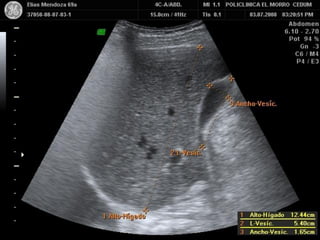

CI HEPATICO CON ASCITIS

INSUFIECIENCIA HEPATICA

HEPATITIS AGUDA FULMINANTE

SOBREHIDRATACION

POR SEPSIS